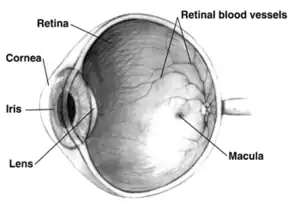

Far-sightedness, also known as long-sightedness, hypermetropia, and hyperopia, is a condition of the eye where distant objects are seen clearly but near objects appear blurred. This blur is due to incoming light being focused behind, instead of on, the retina due to insufficient accommodation by the lens.[6] Minor hypermetropia in young patients is usually corrected by their accommodation, without any defects in vision.[2] But, due to this accommodative effort for distant vision, people may complain of eye strain during prolonged reading.[2][7] If the hypermetropia is high, there will be defective vision for both distance and near.[2] People may also experience accommodative dysfunction, binocular dysfunction, amblyopia, and strabismus.[3] Newborns are almost invariably hypermetropic, but it gradually decreases as the newborn gets older.[6]

There are many causes for this condition. It may occur when the axial length of eyeball is too short or if the lens or cornea is flatter than normal.[2] Changes in refractive index of lens, alterations in position of the lens or absence of lens are the other main causes.[2] Risk factors include a family history of the condition, diabetes, certain medications, and tumors around the eye.[5][4] It is a type of refractive error.[5] Diagnosis is based on an eye exam.[5]

- Axial: Axial hypermetropia occur when the axial length of eyeball is too short. About 1 mm decrease in axial length cause 3 diopters of hypermetropia.[2] One condition that cause axial hypermetropia is nanophthalmos.[11]

- Curvatural: Curvatural hypermetropia occur when curvature of lens or cornea is flatter than normal. About 1 mm increase in radius of curvature results in 6 diopters of hypermetropia.[2] Cornea is flatter in microcornea and cornea plana.[11]

Far-sightedness is often present from birth, but children have a very flexible eye lens, which helps to compensate.[13] In rare instances hyperopia can be due to diabetes, and problems with the blood vessels in the retina.[1]

A diagnosis of far-sightedness is made by utilizing either a retinoscope or an automated refractor-objective refraction; or trial lenses in a trial frame or a phoropter to obtain a subjective examination. Ancillary tests for abnormal structures and physiology can be made via a slit lamp test, which examines the cornea, conjunctiva, anterior chamber, and iris.[14][15]